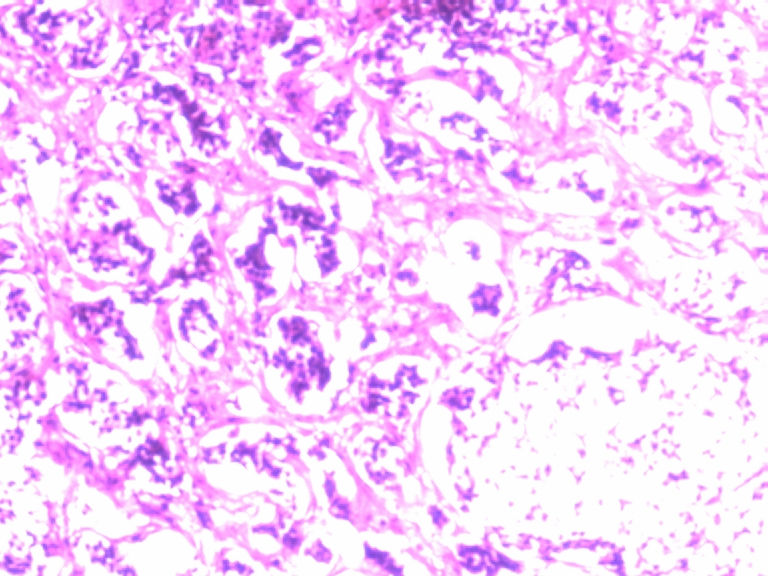

男,50岁,阑尾长7厘米,直径0.4---0.6厘米。剖开:尖端看见淡黄色区,不规则,界限欠清,0.15*0.2厘米,质中。

• 您看了吗?阑尾类癌?图1

图1

考虑阑尾类癌

像类癌,有些粘液,标记一下Syn、CgA,有可能是杯状细胞类癌

按照胃肠胰腺神经内分泌肿瘤WHO2010分类,该例应属于NET G1(神经内分泌瘤,1级)。需标记Syn, CgA, Ki67.

倾向神经内分泌肿瘤,建议做CgA、SYN、Ki-67检查。

阑尾的神经内分泌肿瘤我们已经碰到好几例了,一般都在阑尾尖端,取材一定要规范,这样可以减少漏诊率。